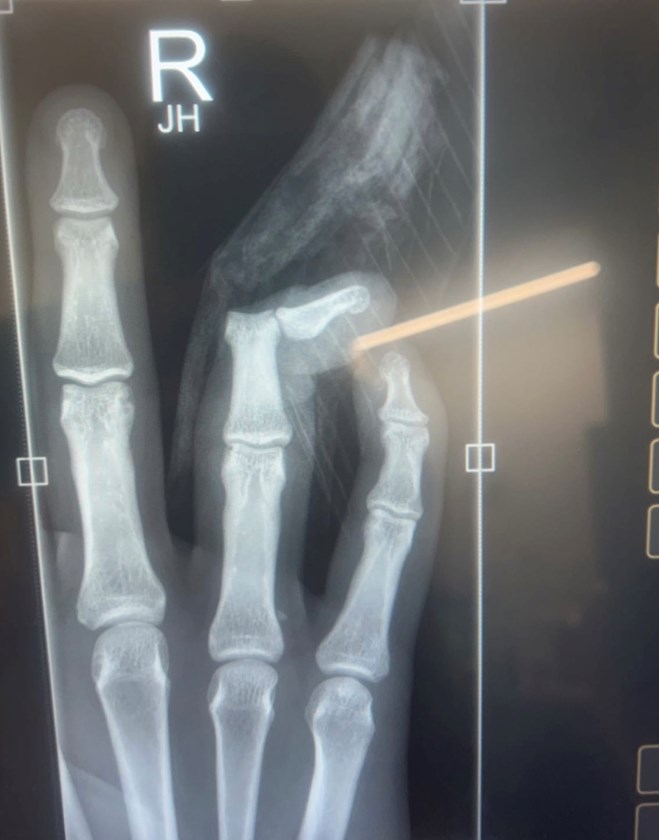

The x-ray of Riley Reid's hand.

“My finger was really badly dislocated,” he said.

“The bone had come out of the socket and that’s why it was poking out of the skin. There was no fracture at all.